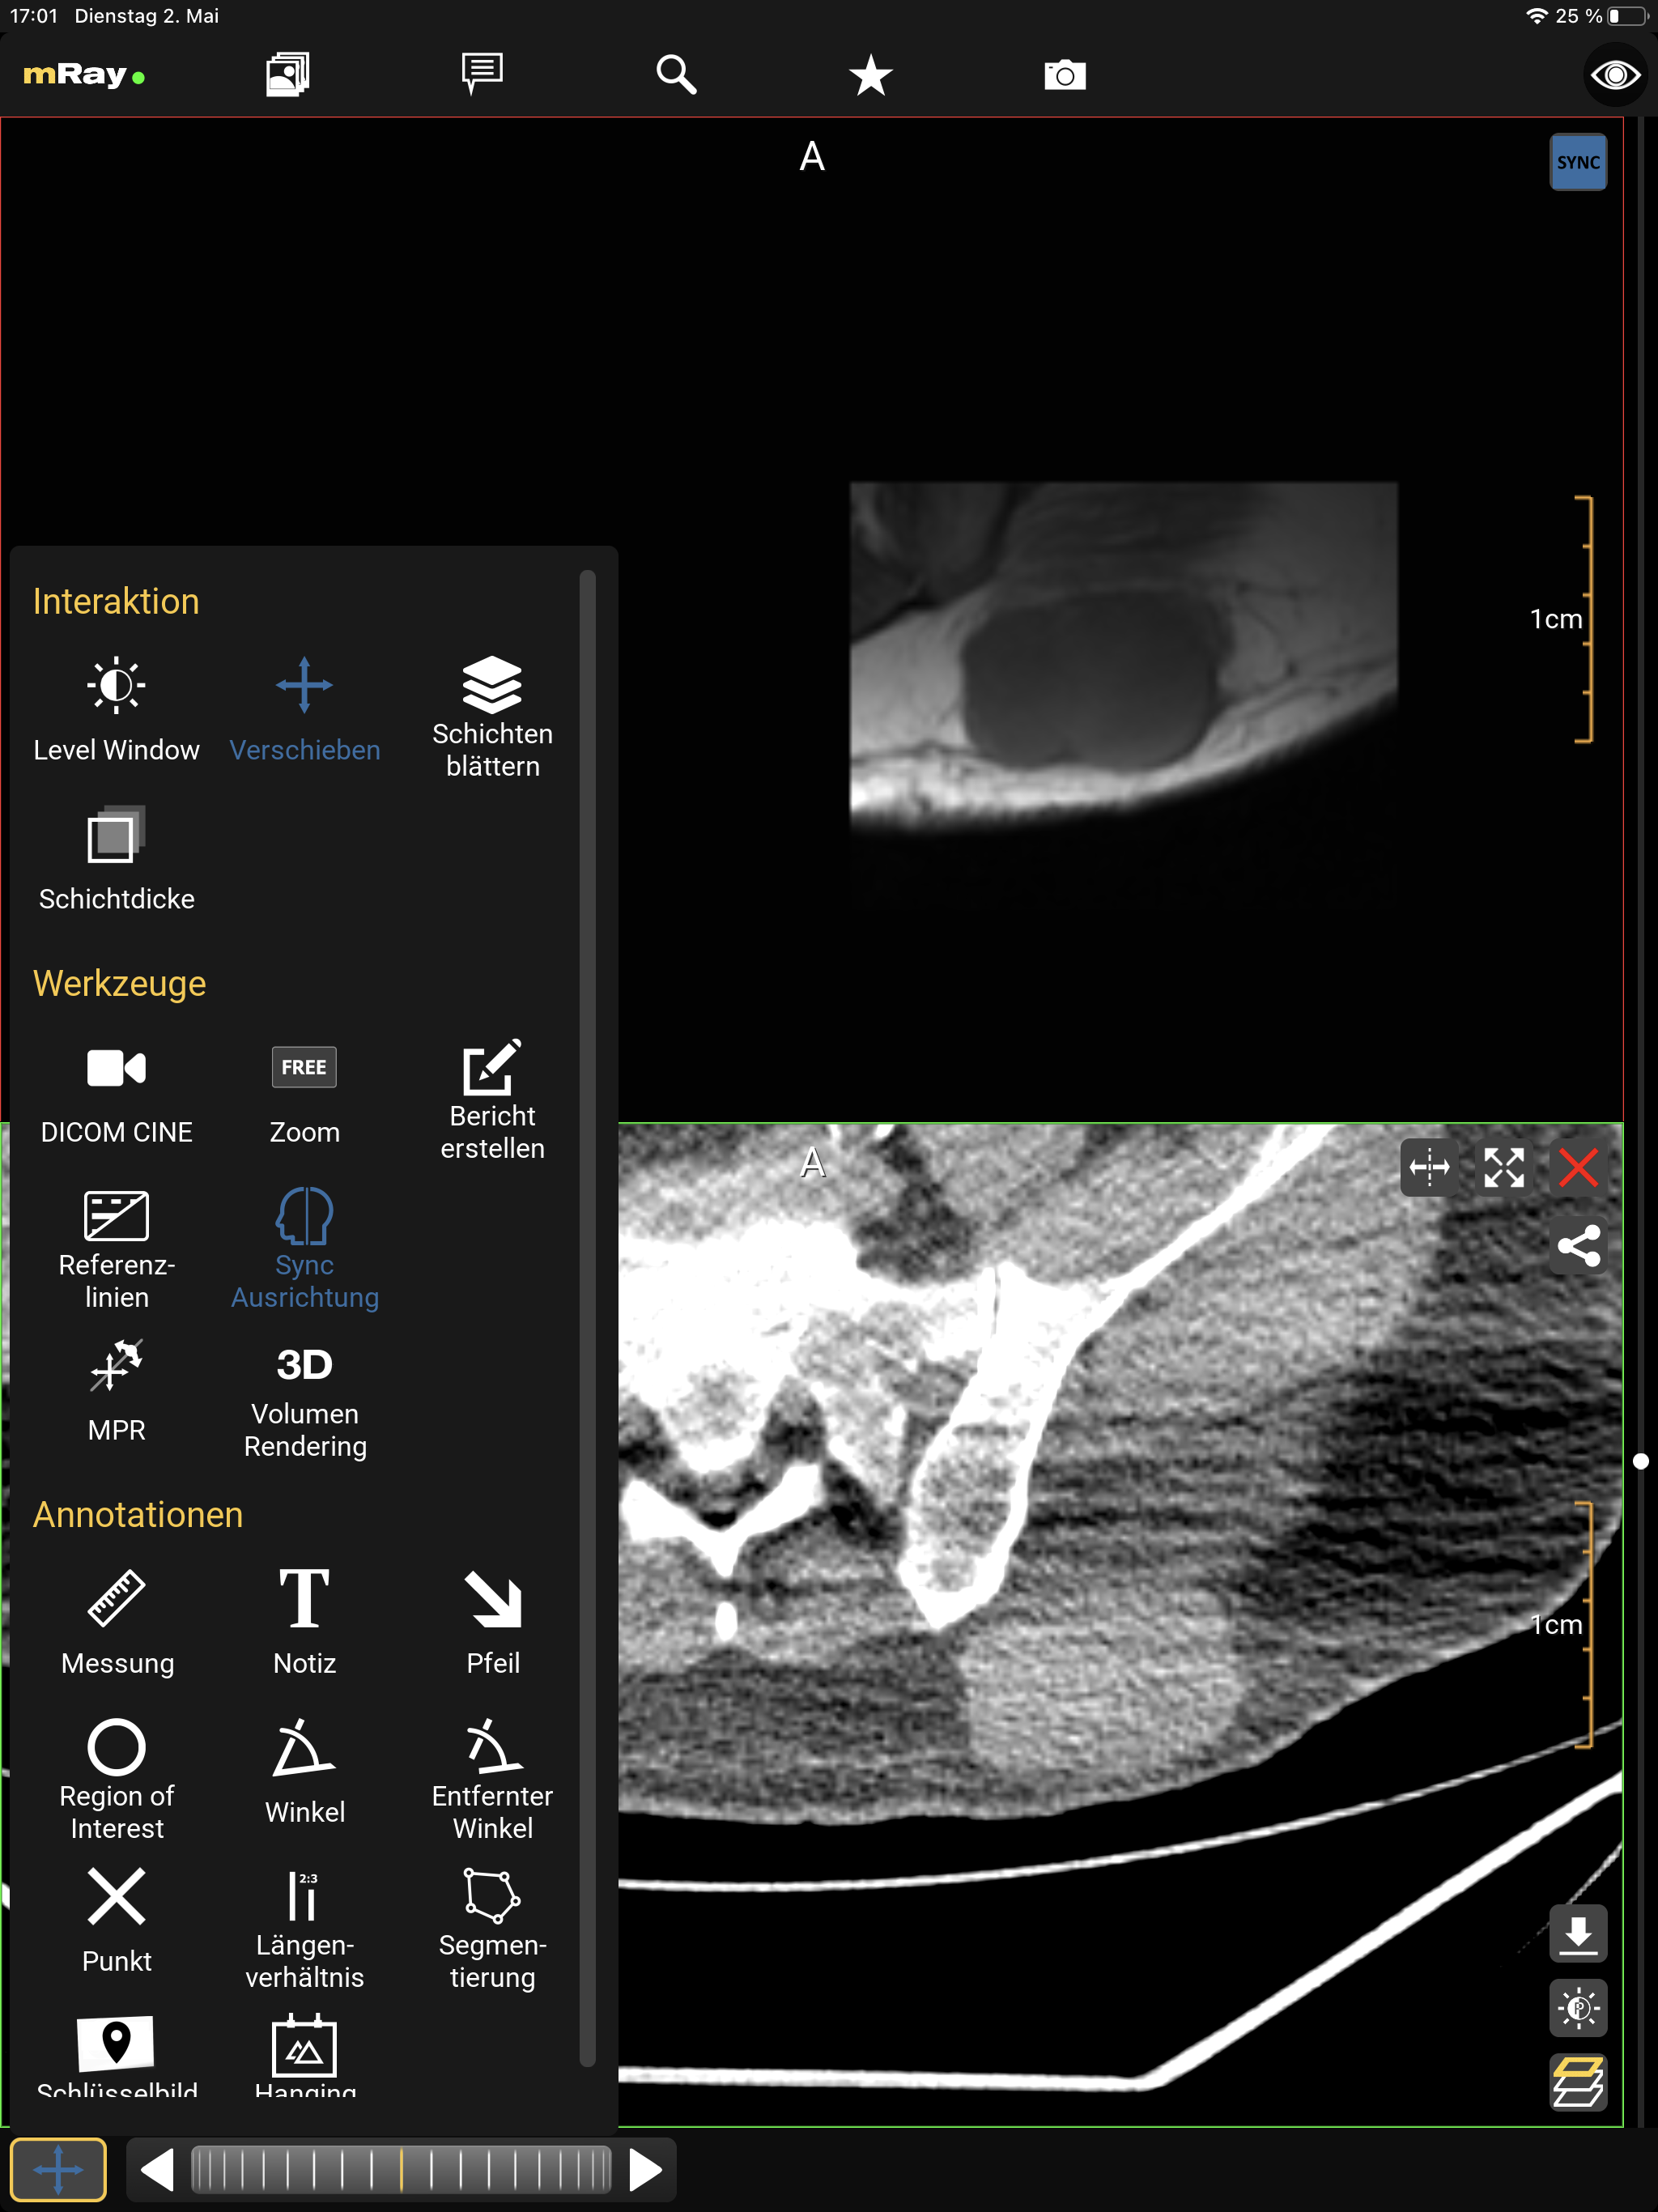

Die MPR-Bildlaufleiste erlaubt es Ihnen, mehrere Ansichten gleichzeitig zu öffnen (MPR-Ansichten). Der folgende Screenshot zeigt die MPR-Bildlaufleiste:

Der Screenshot zeigt die MPR-Bildlaufleiste eines MRTs von einem Fuß, die lokal berechnete Rekonstruktion (MPRs) und Informationen zum angezeigten Datensatz.

Sie können die Perspektive mit dem "MPR-Perspektive"-Button (Punkt 2) verändern. Diese Funktion erlaubt es, zwischen Axial, Sagittal und Coronal zu wechseln. Der Button in der rechten unteren Ecke (Punkt 1) ermöglicht das Öffnen oder Schließen von weiteren Ansichten. Falls mehr als eine Ansicht geöffnet ist, erscheint ein Button um diese zu synchronisieren (siehe Synchronisierte Ansichten). Um mit der Ansicht interagieren zu können, müssen Sie entsprechende Ansicht zunächst auswählen. Dazu müssen Sie die Ansicht nur antippen. Die ausgewählte Ansicht wird dann hervorgehoben.